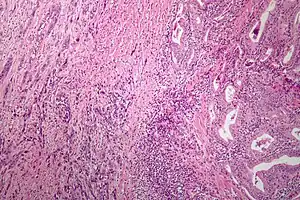

| Microscopic image of anaplastic thyroid carcinoma. H&E stain. | |

Anaplastic tumors have a high mitotic rate and frequently invades the local blood and lymphatic vessels.[5] Cellular death is frequently visualized on microscopic images.[2] The presence of regionally swollen lymph nodes in older patients in whom needle aspiration biopsy reveals characteristic vesicular appearance of the nuclei supports a diagnosis of anaplastic carcinoma. Microscopic images of ATC usually show inflammatory cells from the immune system such as T cells and macrophages.[2]

ATC is divided into several different subclasses based on its microscopic characteristics. These include sarcomatoid, squamoid, osteoclastic, paucicellular, rhabdoid, and carcinomasarcoid variants.[2] As of 2019, despite the fact that these ATC subtypes are recognized, this classification has not led to differences in management.[2] ATC is always considered to be stage IV when it is diagnosed.[6]

Anaplastic thyroid carcinoma cells